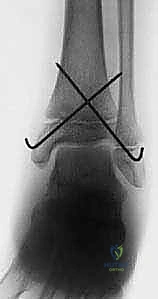

- الأشعة السينية (X-rays): هي الخطوة الأولى والأساسية. يتم التقاط صور من زوايا متعددة (أمامية، جانبية، ومائلة) لتقييم الكسر.

- الأشعة المقطعية ثلاثية الأبعاد (3D CT Scan): تُعد ضرورة حتمية في حالات كسور تيلوكس والكسور ثلاثية المستويات، أو أي كسر يمتد داخل المفصل. توفر الأشعة المقطعية خريطة دقيقة لحجم القطع العظمية ومقدار التباعد (Displacement)، مما يساعد في التخطيط الجراحي المسبق.